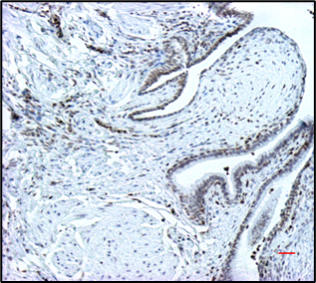

Slide of increased stain (brown) of histone H4K16Ac in lung

Image at right shows increased stain (brown) of histone H4K16Ac in lung tissues from an IPF patient.